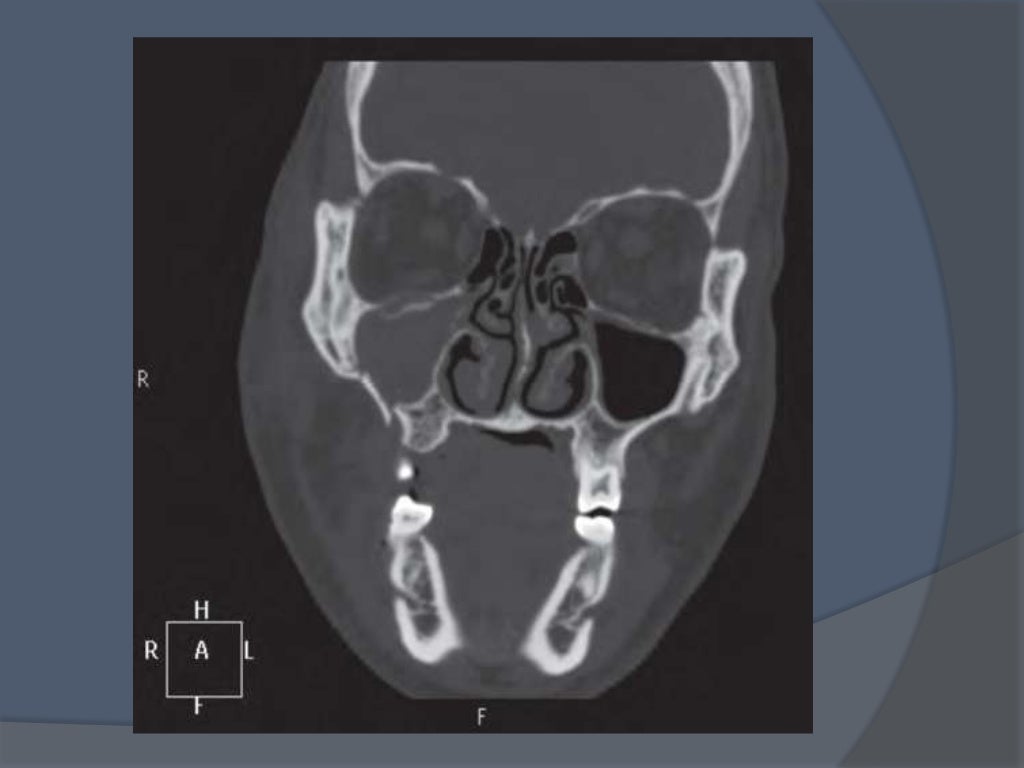

El arco cigomático es una parte del cráneo humano, más concretamente de la cara humana. El arco cigomático se forma en la unión de la apófisis cigomática del hueso temporal propio de los huesos del cráneo y la articulación del apófisis malar, propio de los huesos de la cara, ubicado a un lado de las fosas orbitales.[1]